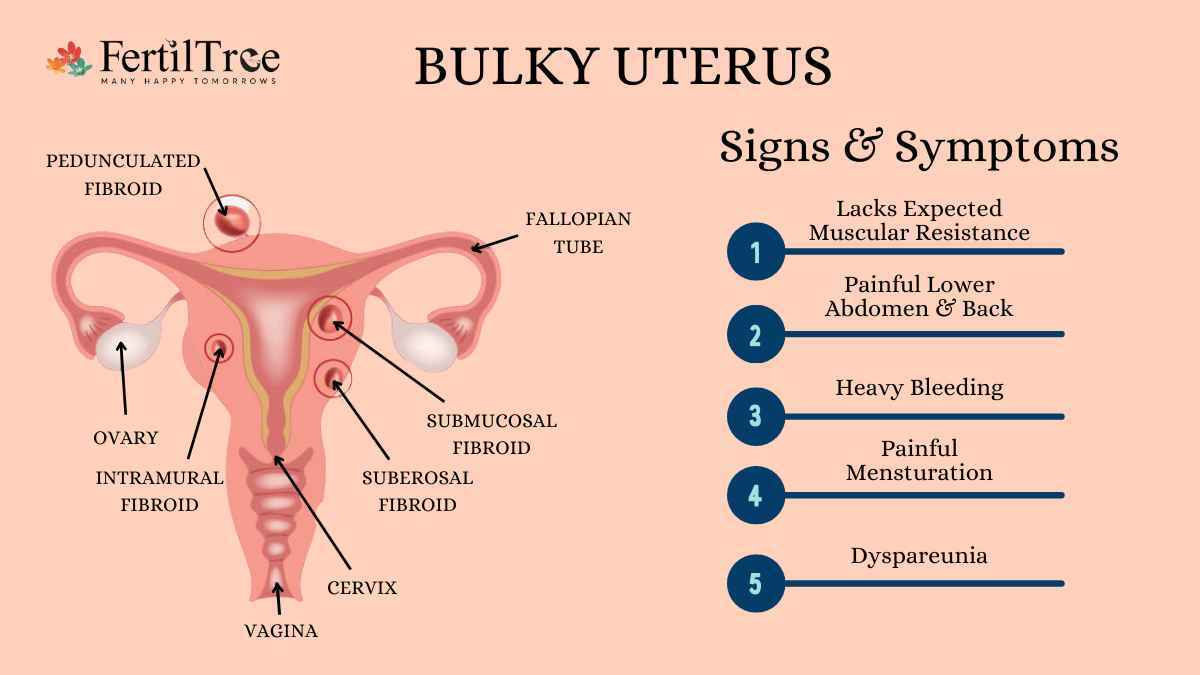

Bulky Uterus Symptoms Causes And Treatment 60 OFF

Fibroids What Are Fibroids

Fibroids What Are Fibroids